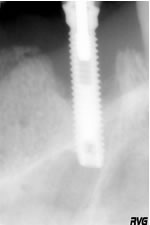

R21 - 16_07_04

Limplant est stabilisé et il y a une reconstitution osseuse (R23 - 18_01_05)

Il ny a plus de suppuration, la douleur à la percussion a disparu, le pilier implantaire (21) nest plus mobile (R21 - 16_07_04).

R23 - 18_01_05